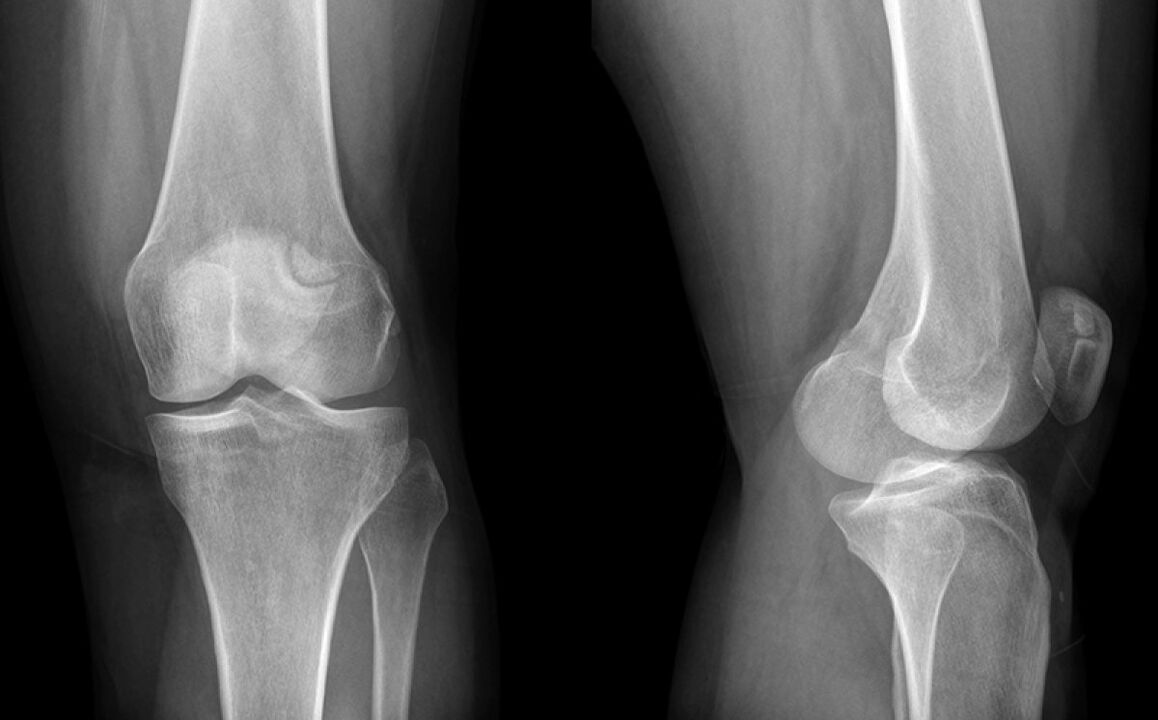

Kolano bolało trzy tygodnie. Ostatecznie poszedłem do lekarza, który podejrzewał uszkodzenie łąkotki i wysłałem na X -Bray. Diagnoza jest początkowym stadium artrozy stawu kolanowego.